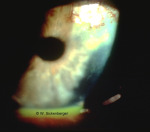

Ulcère cornéen

/1_VAA/5_HH/Ulcus/56(1).jpg

/1_VAA/5_HH/Ulcus/56(2).jpg